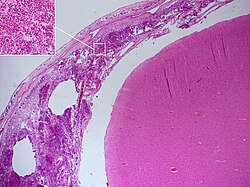

[[Datoteka:Meningitis Histopathology.jpg|mini|250px|Patohistološki nalaz kod bakterijskog meningitisa: obdukcijski nalaz osobe s pneumokoknim meningitisom, u uzorku tkiva se nalazi upalni eksudat koji se sastoji od neutrofilnih granulocita (umetnuto veće povećanje) u mekim moždanim ovojnicama.]] Meningitis se može dijagnosticirati i nakon smrti. Na [[obdukcija|obdukciji]] se obično nalazi opsežna upala meke moždane ovojnice (''Pie mater)'' i paučinaste moždane ovojnice (''Arachnoidee''). [[Neutrofilni granulociti]] koji su dospjeli u cerebrospinalnu tekućinu i na bazu mozga, okružuju i [[moždani živci|moždane živce]] i [[Kralježnična moždina|kralježničku moždinu]], koji mogu biti okruženi [[gnoj|gnojem]] — kao i krvne žile u moždanim ovojnicama.<ref name="OTM1">{{ | [[Datoteka:Meningitis Histopathology.jpg|mini|250px|Patohistološki nalaz kod bakterijskog meningitisa: obdukcijski nalaz osobe s pneumokoknim meningitisom, u uzorku tkiva se nalazi upalni eksudat koji se sastoji od neutrofilnih granulocita (umetnuto veće povećanje) u mekim moždanim ovojnicama.]] Meningitis se može dijagnosticirati i nakon smrti. Na [[obdukcija|obdukciji]] se obično nalazi opsežna upala meke moždane ovojnice (''Pie mater)'' i paučinaste moždane ovojnice (''Arachnoidee''). [[Neutrofilni granulociti]] koji su dospjeli u cerebrospinalnu tekućinu i na bazu mozga, okružuju i [[moždani živci|moždane živce]] i [[Kralježnična moždina|kralježničku moždinu]], koji mogu biti okruženi [[gnoj|gnojem]] — kao i krvne žile u moždanim ovojnicama.<ref name="OTM1">{{Citiranje knjige | title=Oxford Textbook of Medicine 3. svezak | author=Warrell DA, Farrar JJ, Crook DWM | chapter = 24.14.1 Bacterial meningitis | year=2003. |publisher=izdavač: Oxford University Press | isbn=0-19-852787-X | pages=str. 1115.–1129. | edition = 4. izdanje }}</ref> | ||

Meningitis se može dijagnosticirati i nakon smrti. Na obdukciji se obično nalazi opsežna upala meke moždane ovojnice (Pie mater) i paučinaste moždane ovojnice (Arachnoidee). Neutrofilni granulociti koji su dospjeli u cerebrospinalnu tekućinu i na bazu mozga, okružuju i moždane živce i kralježničku moždinu, koji mogu biti okruženi gnojem — kao i krvne žile u moždanim ovojnicama.[35]